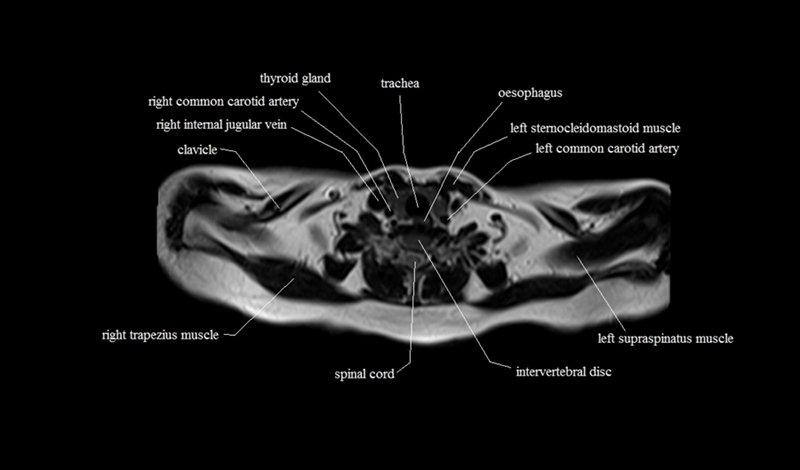

MRI Axial Cross Sectional Anatomy of Chest

This MRI chest (thorax) axial cross sectional anatomy tool is absolutely free to use. Use the mouse scroll wheel to move the images up and down, or alternatively, use the tiny arrows (→) on both sides of the image to navigate through the images. For a more detailed view, double-click the image to view it in full screen, and use the menu in the top right-hand corner to view individual slides or play them in a loop.